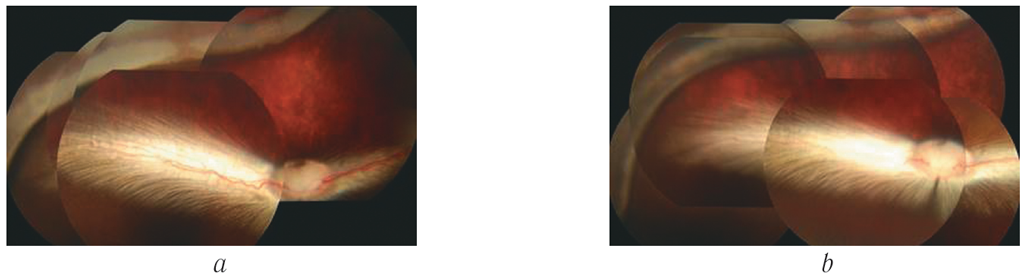

При выполнении офтальмоскопии глазного дна сетчатка была интактна, за исключением зоны нахождения дренажной полиуретановой трубки в супрахориоидальном пространстве, где в первые сутки после операции отмечался локальный ишемический отёк сетчатки по валу вдавления и в зоне периферичнее одного линейного размера поперечника вала вдавления. При контрольной офтальмоскопии на пятые сутки явления ишемии купировались — регрессировал ишемический отёк сетчатки (восстанавливалась естественная окраска внутриглазных оболочек) (рис. 7). Признаки нагноения, отторжения и обнажения имплантата, суб- и интраретинальных кровоизлияний, гемофтальма отсутствовали в течение всего периода наблюдения.

Рис. 7. Офтальмоскопическая картина на первые (а) и пятые (b) сутки после оперативного вмешательства

Fig. 7. Ophthalmoscopic findings on Day 1 (a) and Day 5 (b) after surgery